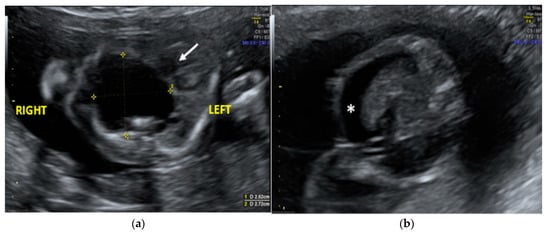

The morphological examination revealed the presence of a large anechoic cystic mass with unregular borders occupying the entire right hemithorax (LD = 2.7 cm; APD = 2.5 cm; TD = 2.4 cm), which apparently originated from the lung parenchyma (Figure 1A). The cyst had no internal or perilesional vascularization. Fetal heart appeared to be anatomically normal, but it was extremely shifted on the left, together with the mediastinum, due to the compression caused by the cyst. The remaining fetal anatomy seemed to be regular, except for the presence of marked ascites (Figure 1B).

Figure 1.

Transabdominal ultrasound managed at 23 weeks of gestational age according to amenorrhea (21.5 weeks according to first ultrasound): (a) Transverse fetal thoracic scan showing the large anechoic cystic formation occupying the entire right hemithorax. Fetal heart (arrow) and mediastinum were extremely shifted on the left due to the cyst compression; (b) transverse fetal transabdominal scan showing marked ascites (*).